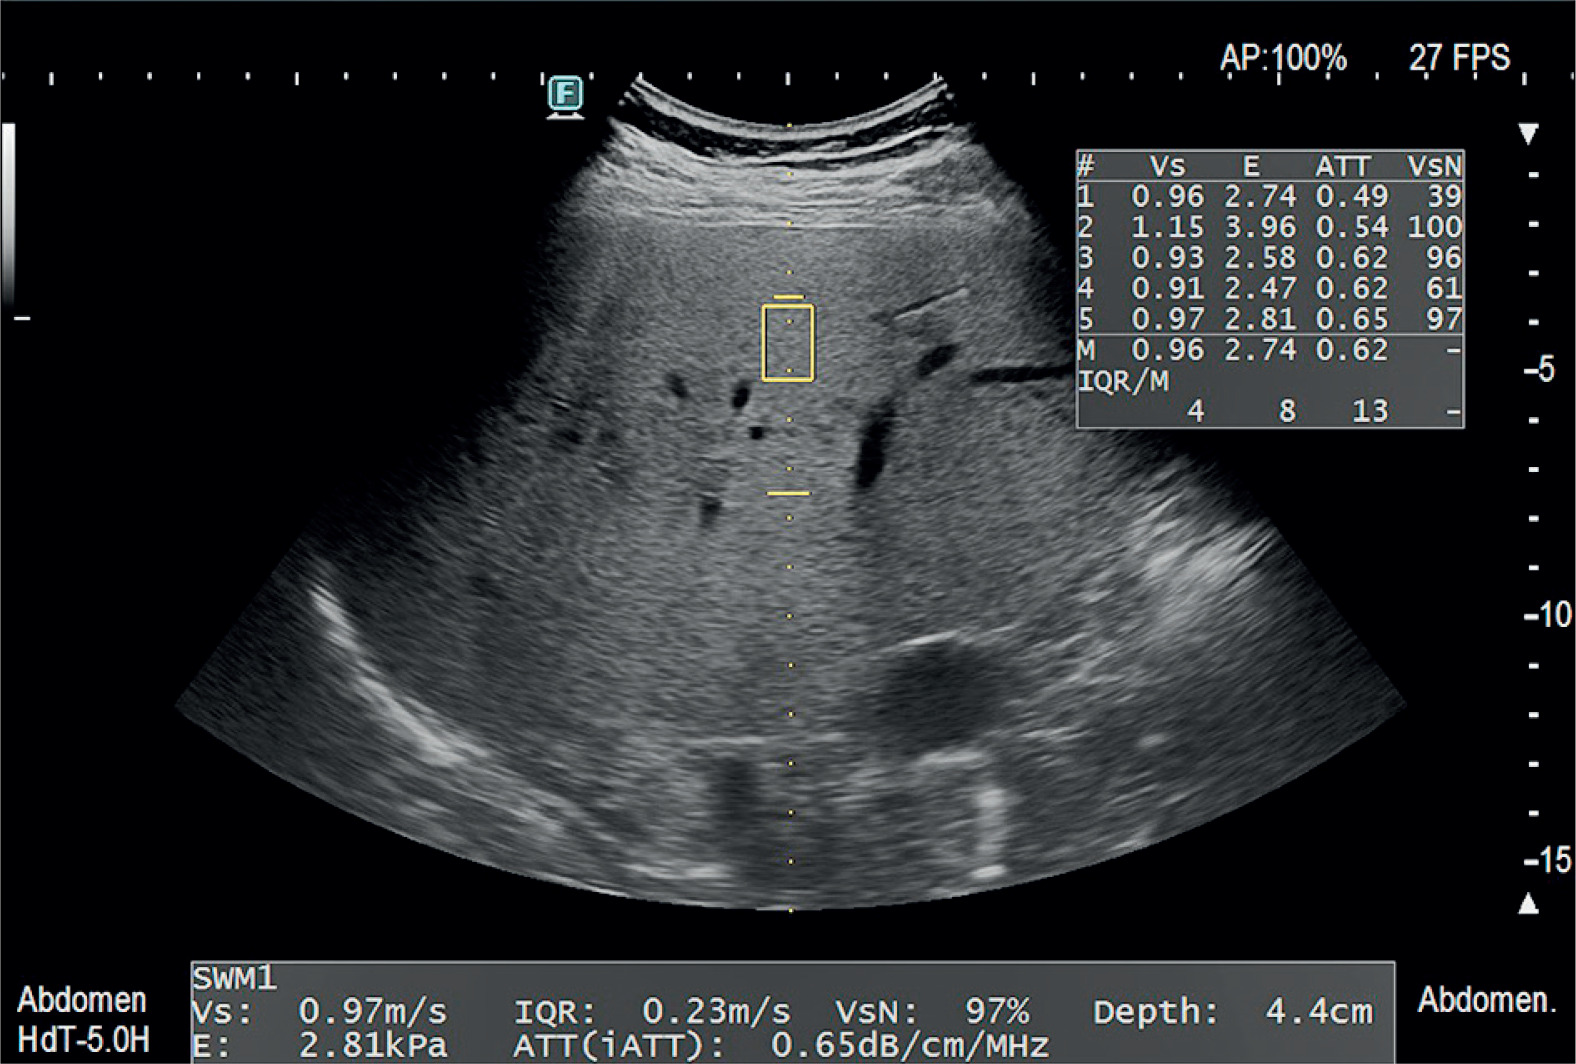

A Fujifilm Arietta 850 device (FUJIFILM Medical Co., Ltd., Tokyo, Japan) with a convex C251 (1.8-5.0 MHz) probe was used. Visual evaluation of the liver in B-mode was performed using the manufacturer’s standard abdominal preset. The point shear wave elastography method, with simultaneous evaluation of the attenuation coefficient (iATT) was used. All examinations were performed in accordance with the WFUMB’s Guidelines/Guidance on Liver Multiparametric Ultrasound. Part 1: Update to 2018 Guidelines on Liver Ultrasound Elastography – 2024 and Guidelines/Guidance on Liver Multiparametric Ultrasound. Part 2: Guidance on Liver Fat Quantification – 2024 [13,14].

The standard protocol for the acquisition of liver stiffness measurement must be followed in accordance with the guidelines when the attenuation coefficient is obtained in conjunction with the measurement of liver stiffness. Patients fasted for 4 h and rested in a sitting position for 10 min before the examination. Then they were placed in a supine position with the right forearm held behind the head and the arm in maximum abduction (180° from the resting position) to widen the intercostal space. Measurements were taken with an intercostal approach at the location with the best acoustical window without shadowing caused by the lung or ribs. The transducer was perpendicular to the liver capsule during the measurement. The measurements were made at a standard depth set by the vendor with the upper edge of the measurement box at least 2 cm below the liver capsule. Blood vessels, bile ducts, and masses were avoided. Measurements were made during a breath-hold while breathing at neutral. Every measurement was made using separate images that were all acquired at the same location. Five attenuation measurements of the right liver lobe were performed for each patient, and the median values and the interquartile range to median ratio (IQR/M) of the acquisitions were reported. An example set of final measurements is shown in Figure 1.

Figure 1

An example of an attenuation coefficient measurement using the iATT method with a Fujifilm Arietta 850 ultrasound